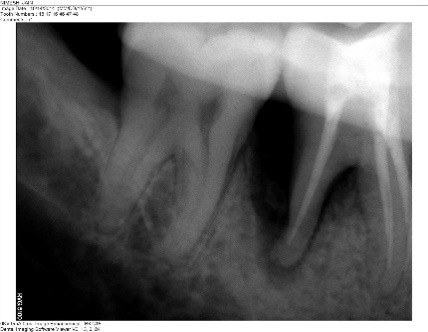

Radiographic evaluations were performed at baseline, six months and one year. The radiographic images were measured using CorelDraw Graphics Suite X6 and the density changes were measured using Adobe Photoshop CS3. The percentage of the defect fill was 44.5% and there was a change in radiodensity of the defect area, suggestive of improvement in newly formed bone (Figures 4 and 5).

Figure 5.Radiovisiograph (RVG) of the right mandibular first molar region at one-year follow-up; radiographic defect fill seen distal to the right mandibular first molar.